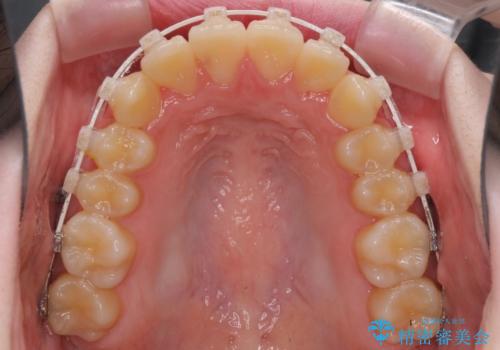

- 上下前歯のデコボコを気にして来院された患者様です。

前歯の叢生は強かったのですが、口元が引っ込んでいる印象であったため、非抜歯にて矯正治療を行うこととしました。

インビザラインでの自己管理は難しいとのことで、ワイヤー装置にて矯正を行うこととしました。